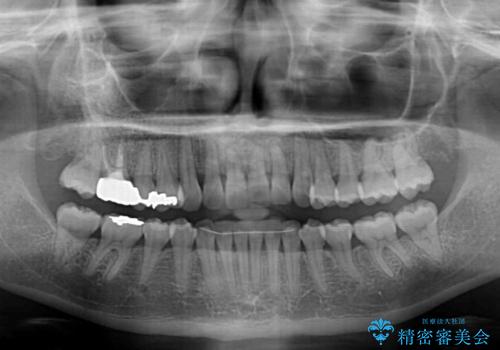

- 1年8ヶ月

- むし歯治療を契機に、長年気にしていた前歯のクロスバイトの改善を希望された患者様です。

汚れが溜まりやすく、歯ぎしりがうまくできないため、インビザラインを用いて矯正治療を行うこととしました。

インビザラインによる前歯のクロスバイトの改善は、治療期間中に前歯でしか咬めない時期が続いたり、歯肉退縮や歯髄壊死のリスクが高まったりと、治療中にトラブルを抱えることがあります。

特に上顎側切歯(真ん中から2番目の歯)が舌側に引っ込んでいるケースは、インビザラインでは改善しきれないことがあると言われています。